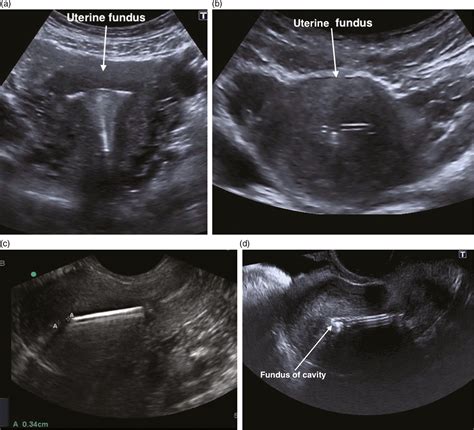

When a physician suspects a perforation, they will typically initiate a diagnostic process to determine the extent of the damage. Imaging technologies play a vital role here. A transvaginal ultrasound is often the first line of defense, as it can help locate an misplaced IUD or detect free fluid in the pelvic cavity that might indicate bleeding. In more complex scenarios, a CT scan or MRI may be required to visualize the abdominal cavity more clearly and rule out injury to the bowel, bladder, or major arteries.

While accidents can happen, there are ways that medical professionals reduce the risk of uterine perforation. These include the use of ultrasound guidance during difficult IUD insertions, performing procedures in a controlled hospital environment, and ensuring the patient is adequately relaxed. Patients can also contribute to safety by being transparent about their medical history, including any previous cesarean sections or uterine surgeries, which helps the physician better prepare for the procedure.